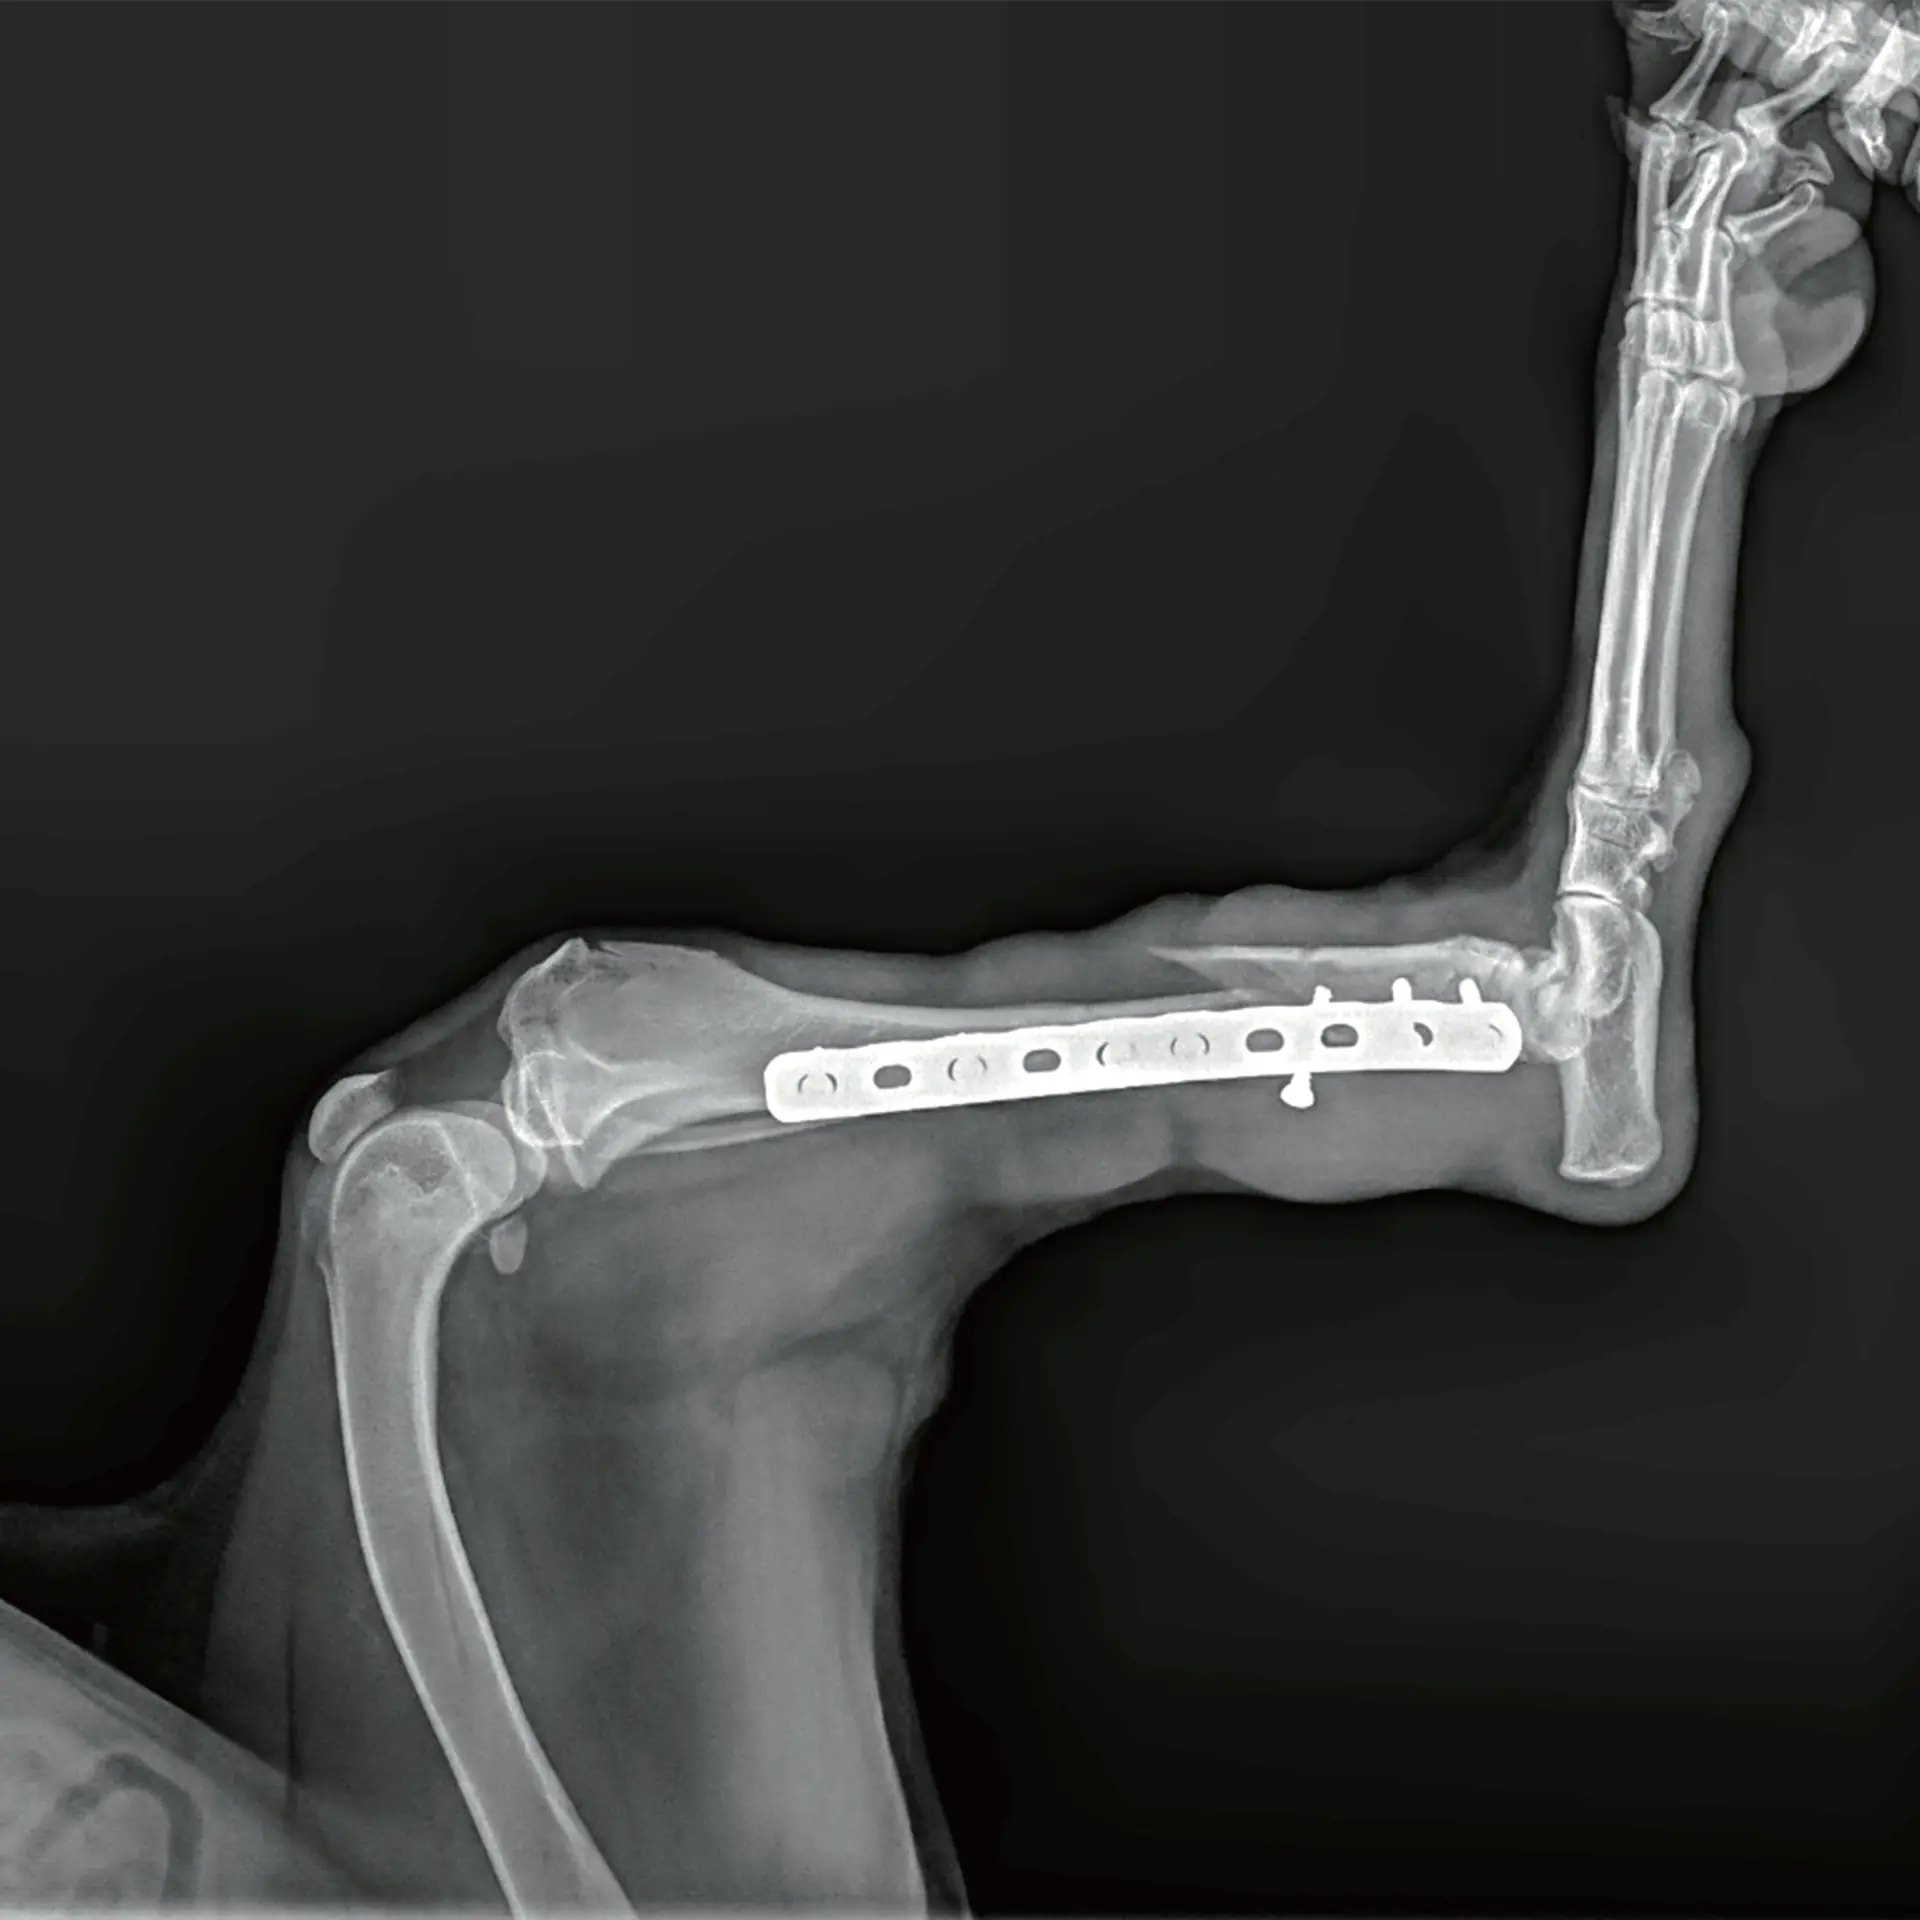

Ortopedik Görüntüleme

Kırık sonrası post-operatif inceleme